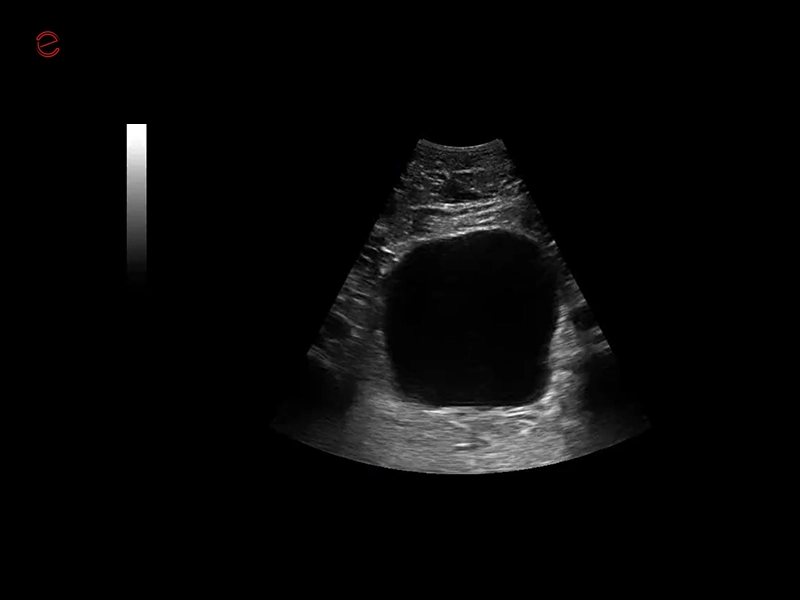

Q7 - GI Kidney

Q7 - GI Kidney